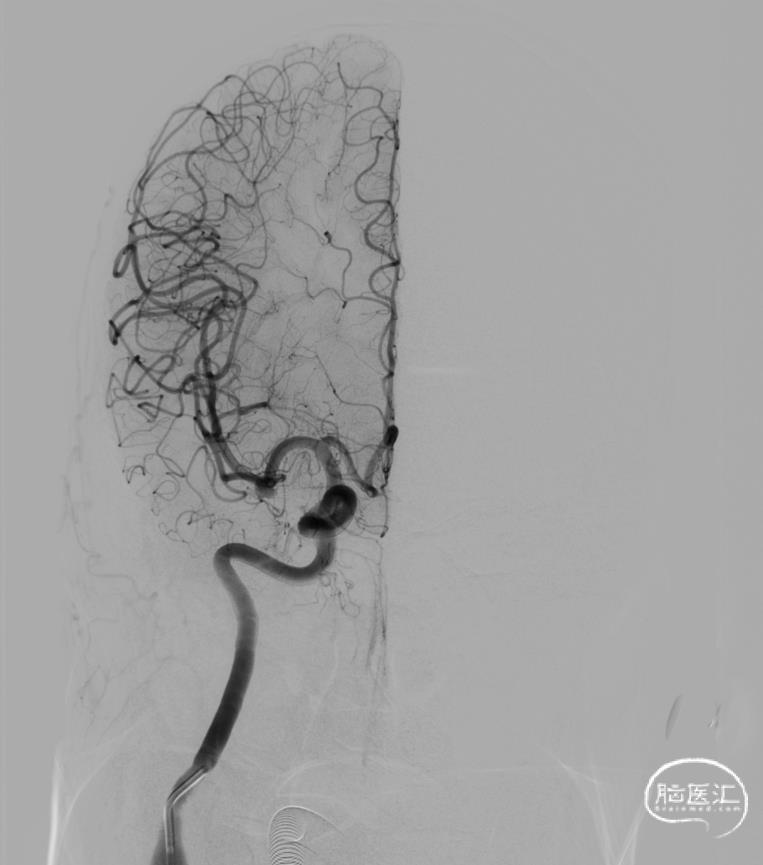

超选右侧ICA正位及侧位造影

动脉瘤位于M1分叉处,三分支。

难点:绝对宽颈,分支需要保护,支架辅助栓塞,可能需要Y支架保护分支。

治疗方式:采用Y型支架辅助弹簧圈栓塞。

策略:支架放在较弯的分支-M1主干,必要时,可再另一分支-M1主干放另一支架,形成Y支架。